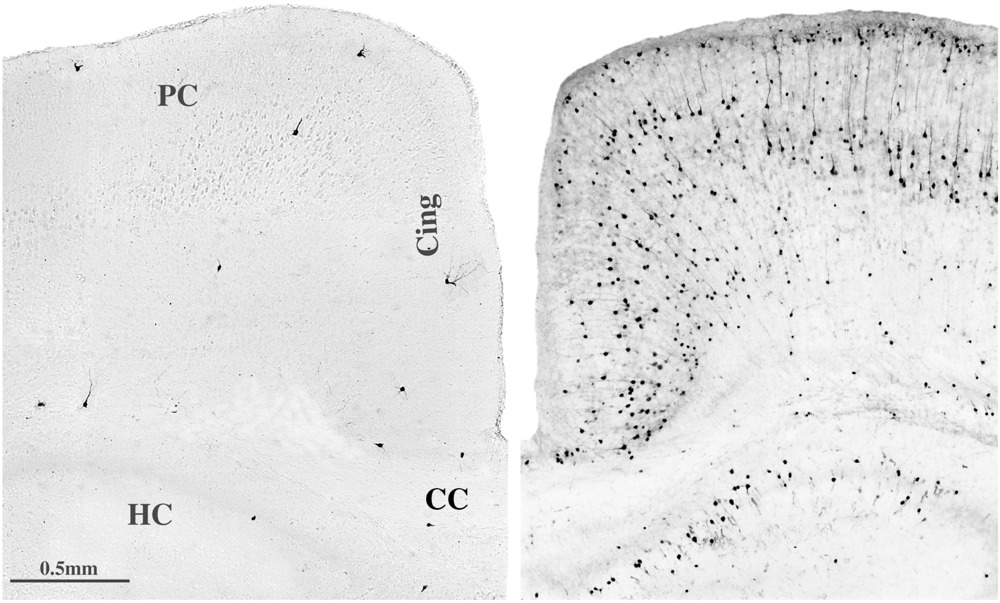

2.1. Neuroapoptosis

2.2. Oligoapoptosis